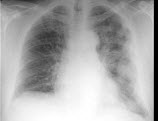

6、单项选择题

男,38岁,咳嗽、胸痛、咯血1天,X线检查如图,最可能的诊断是()